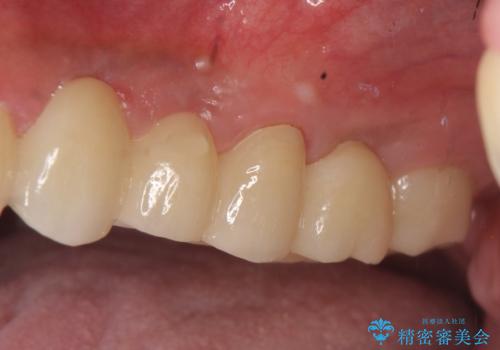

インプラントは希望されなかったため、左側は1番から7番のロングスパンブリッジによる補綴を行いました。

オールセラミッククラウンについて

今回用いたオールセラミッククラウンは、ジルコニアフレームという白い素材の上にセラミックを盛っているため審美性が非常に高いのが特徴です。

またジルコニアは人工ダイヤモンドの材料にも使われているほど高い強度を持っており、そのためオールセラミッククラウンは審美性だけでなく、奥歯やブリッジの補綴も可能とするクラウンです。